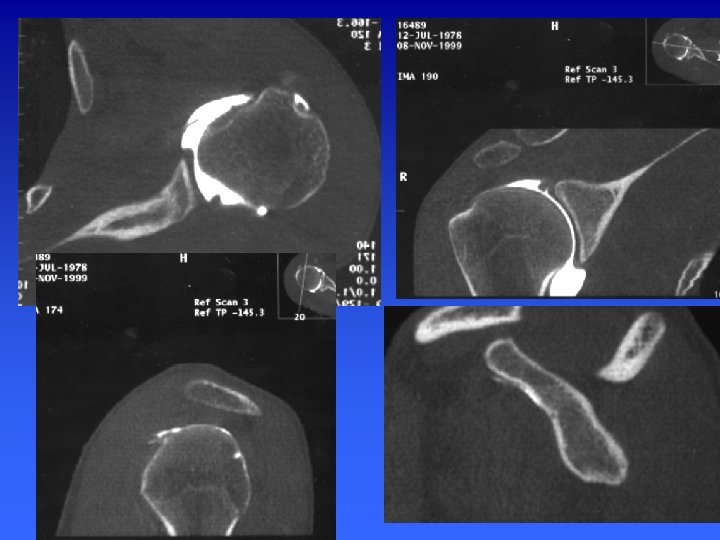

Arthroscanner Indications Actuellement l’examen de référence dans : Les instabilités gléno-humérales La pathologie de la coiffe des rotateurs Cependant il n’explore pas la face superficielle des tendons et ne permet pas le diagnostic des lésions intratendineuses

Arthroscanner 1 er temps : arthrographie classique 2éme temps : acquisition hélicoïdale millimétrique, pitch de 1 à 1, 5 et un incrément de reconstruction de 0, 5 mm. Reconstructions multiplanaires (MPR) sagittales et frontales obliques.

ARTHROSCANNER EPAULE n Positionnement : épaule en position neutre n Topogramme : art acromio-clav - pointe omoplate n Acquisition : hélicoïdale millimétrique de l’articulation acromioclav jusqu’au rebord inf de la glène n Pitch de 1 à 1, 5 et un incrément de reconstruction de 0, 5 mm. W= 2500/600

ARTHROSCANNER EPAULE n Reformatage Axial perpendiculaire à la glène n Para-saggitales dans le plan d’obliquité de la glène n Para-frontal, perpendiculaire au plan de la glène n

Représentation schématique de la coupe d’arthroscanner passant par le pôle supérieur de la tête humérale